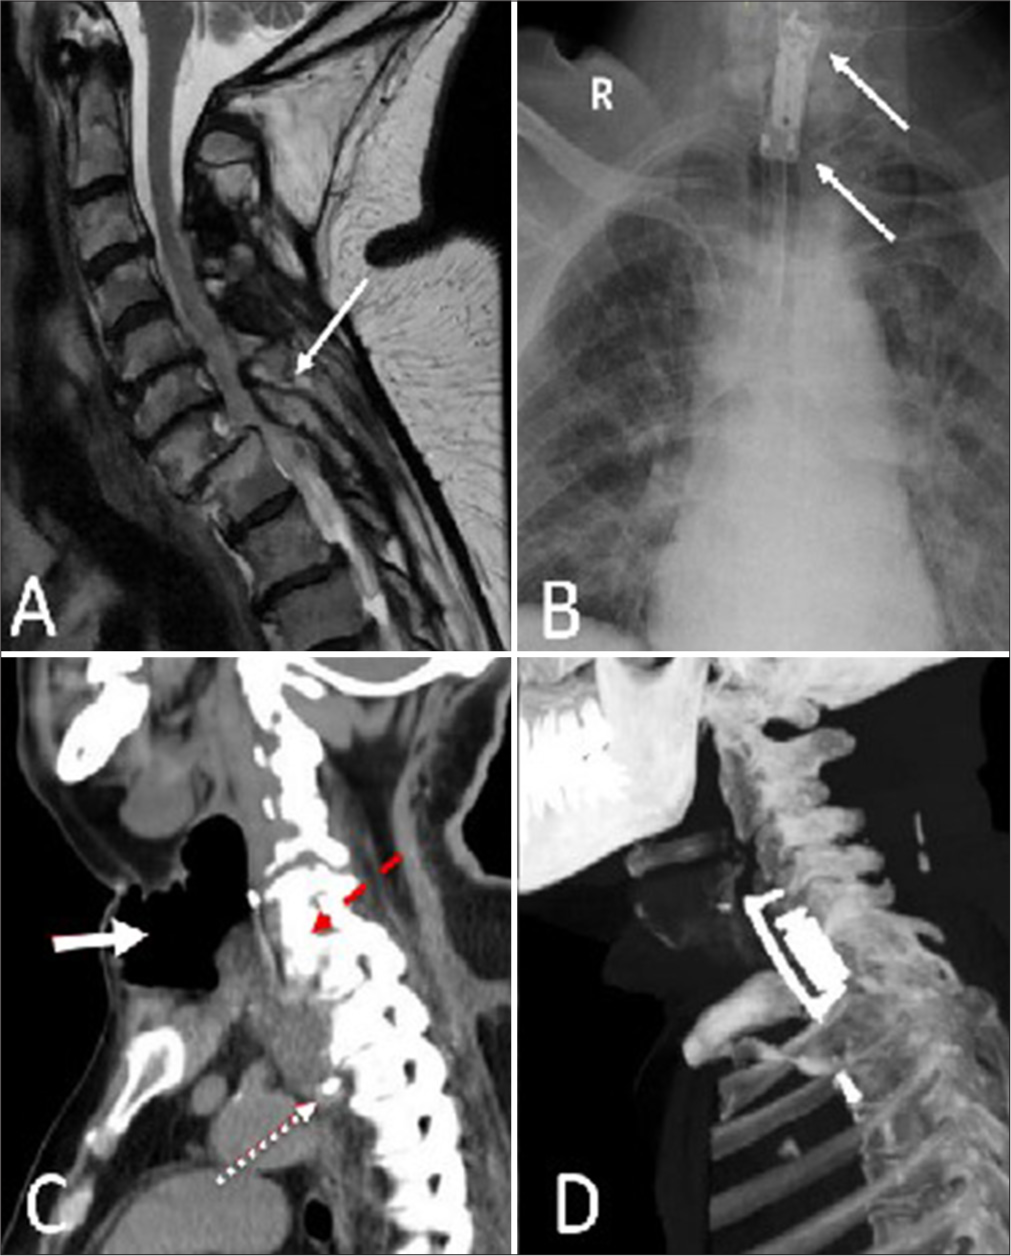

Rudolph Muliawan Putera, Achmad Firdaus Sani